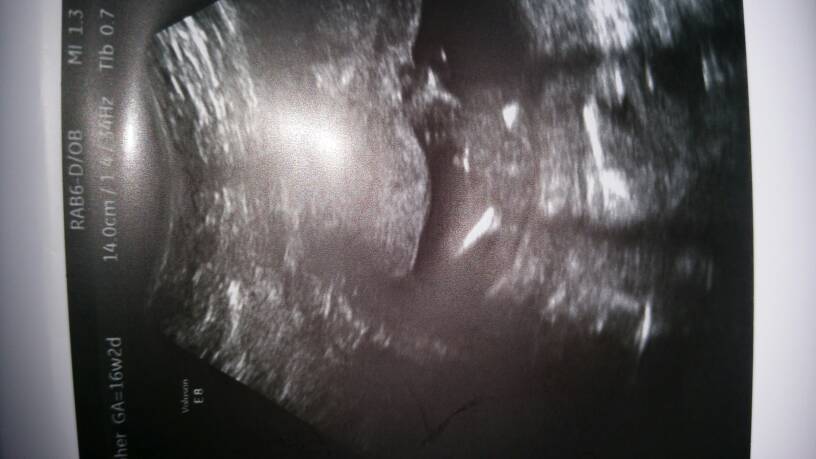

Which gestation is this? Still thinking boy though :)

It's 16 weeks

Maybe boy. Could you zoom out please?